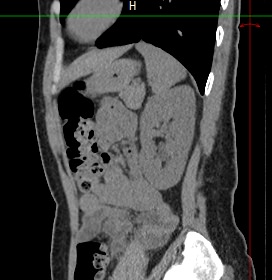

Мультиспиральная компьютерная томография почек и мочевыводящих путей является высокоинформативным методом исследования, основанном на использовании воздействия рентгеновских лучей на органы и ткани человека. Методика предусматривает послойное сканирование области почек, мочевыводящих путей и получение снимков исследуемой области в мельчайших подробностях.

В клинике «Доступная медицина» исследование проводится с помощью современного мультиспирального 128-срезового томографа TOSHIBA AQUILION CXL, который производит сканирование области почек в виде тончайших срезов с шагом от 0,5 мм, затем обрабатывает полученные данные и выдает трехмерные изображения отсканированной зоны.

Увеличенное количество детекторов, расположенных в томографе по спирали, обусловливает проведение исследования за короткий период времени, что значительно снижает лучевую нагрузку на организм пациента. Процедура отличается быстротой, безболезненностью и максимальной информативностью.